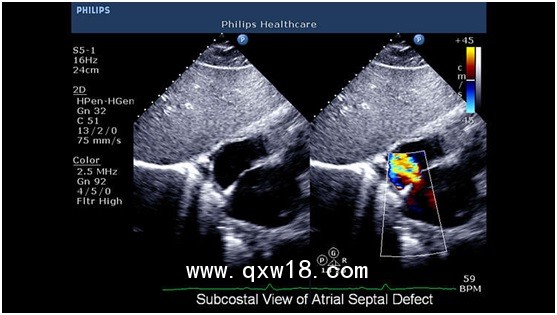

CX50可移動(dòng)高集成超聲診斷系統(tǒng) 引領(lǐng)超聲新浪潮,CX50是市場(chǎng)上第一款高集成的移動(dòng)超聲診斷系統(tǒng),它將大型高檔彩超iE33/iU22的優(yōu)異平臺(tái)與便攜性能集于一身,為患者提供更高品質(zhì)的醫(yī)療服務(wù),更靈活的移動(dòng)選擇,提高醫(yī)師的工作效率。

2? 心臟超聲